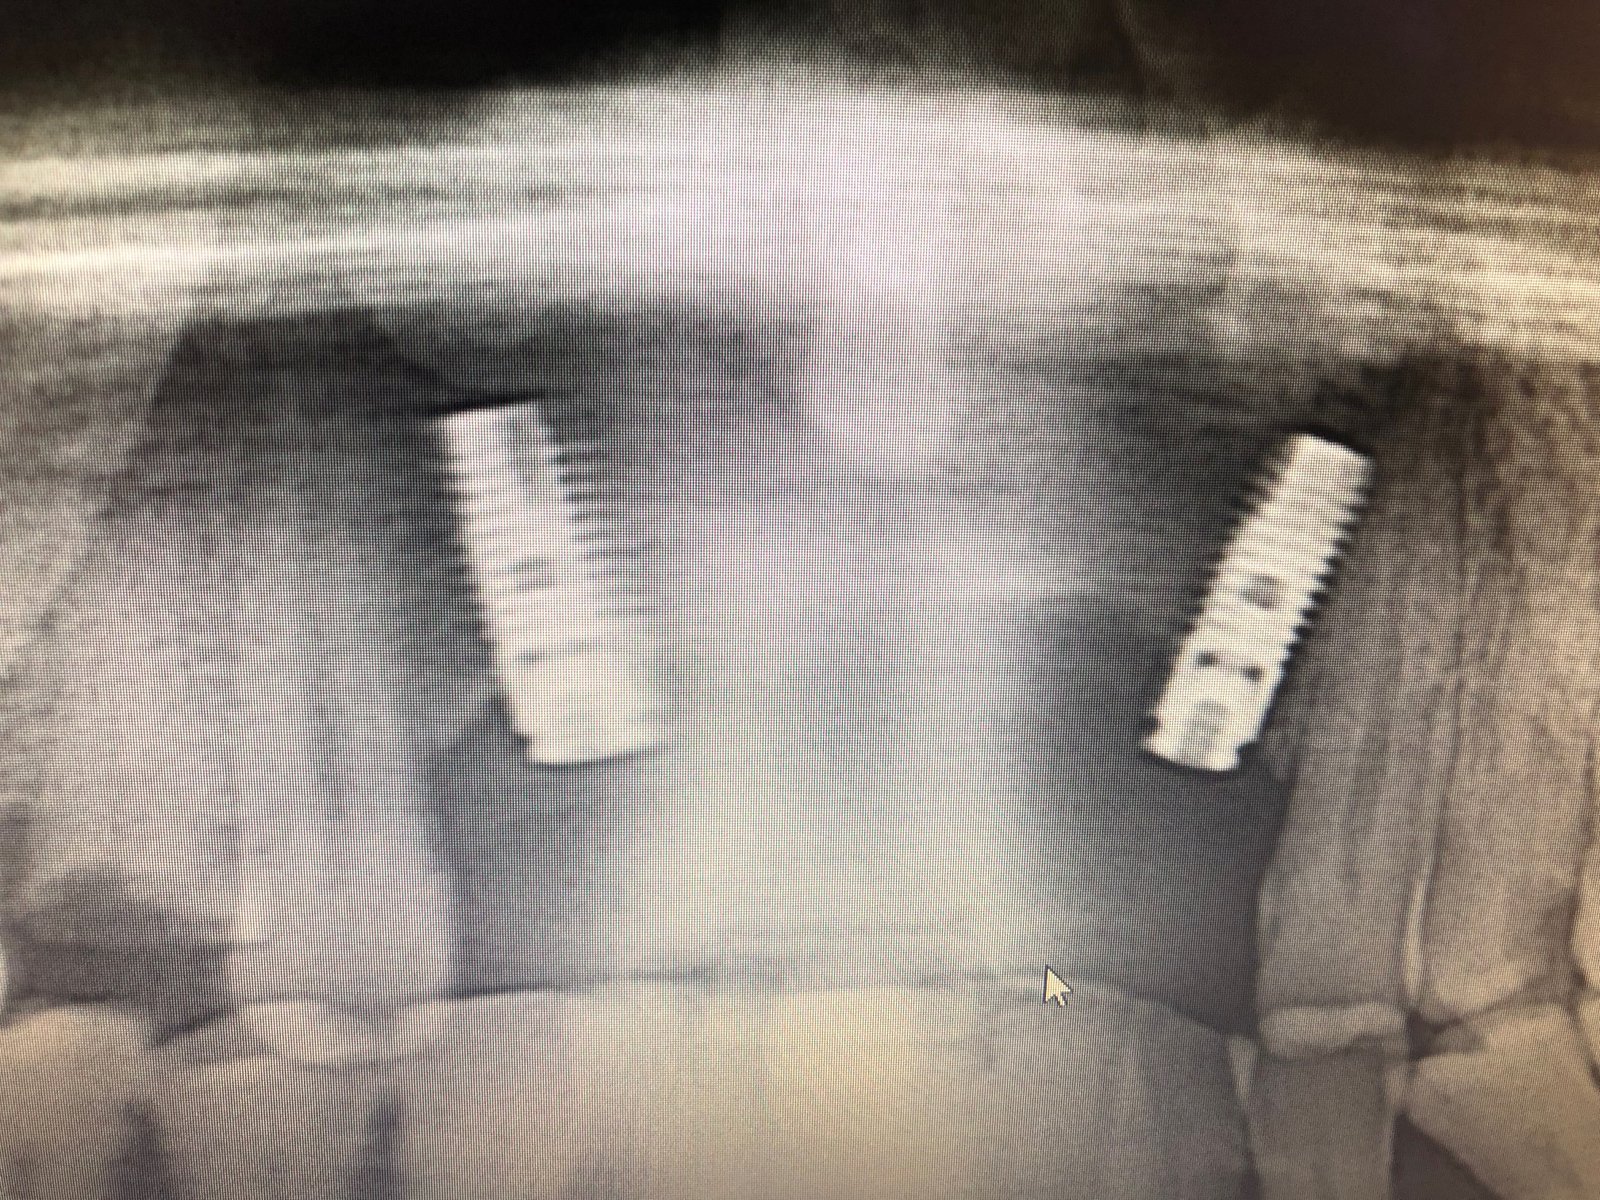

Buenas tardes, ¿me podria algun decir que tipo de conexion y marca de implante es? muchisismas gracias de antemano!

Por favor! Alguien sabe que marca de implante es? Gracias!